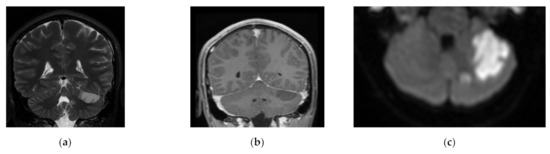

3.2. CT and MRI Reports